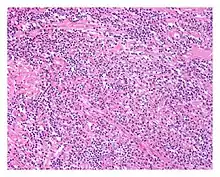

| Low power view of IgG4-related prostatitis. The prostatic stroma shows a dense inflammatory infiltrate and fibrosis (H&E, 100x) | |

The diagnosis of IgG4-related prostatitis could be made from histological examination if prostate biopsy or surgery has been performed.[6] The hallmark histopathological features of established IgG4-related disease are storiform fibrosis, a dense lymphoplasmacytic (lymphocytes and plasma cells) infiltrate rich in IgG4-positive plasma cells, and obliterative phlebitis.[7]